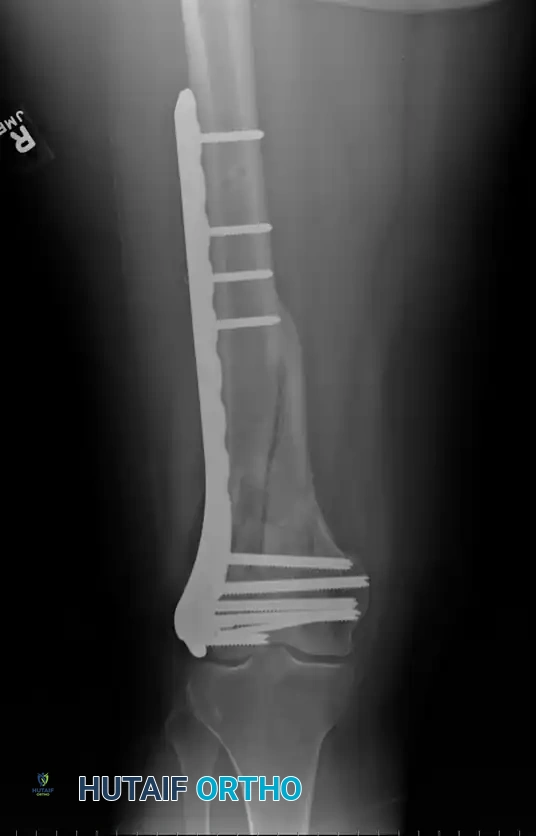

Fig. 51-78 Fifty-year-old patient with a displaced comminuted supracondylar fracture of the femur internally fixed with an AO supracondylar blade plate and multiple screws.

Schatzker and Lambert highlighted the technical difficulty of this implant, noting that good results were obtained in 71% of fractures with stable fixation, but plummeted to 21% if fixation was inadequate. Siliski, Mahring, and Hofer later reported 81% good or excellent results in severe Type C fractures using blade plates, though intentional shortening of 1 to 3 cm was often required in older patients to achieve bony apposition and stability.